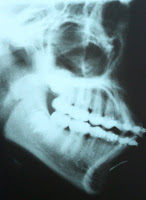

Se realizó una evaluación radiográfica revelando una radioopacidad bastante bien definida de 1cm aproximadamente. Se decidió realizar cirugía exploratoria para recuperar la barra. (Figura 2)